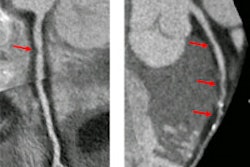

Transthoracic echocardiographic imaging was performed on the athletes to measure their myocardial structure and function. The authors took aortic measurements in triplicate over three cardiac cycles.

Out of the male athletes, almost one-third had at least one aortic dimension of 40 mm or larger; however, the findings varied by sport. Male rowers accounted for 61% of athletes with an enlarged aorta. The rowers also had a significantly larger raw aortic size and ascending aorta than male runners.

The difference in aortic dilation between male rowers and runners could be explained by the cardiovascular activity requirements of each sport, the authors noted. For instance, running requires sustained, even cardiovascular activity, whereas rowing requires different levels of strain during the stroke motion.